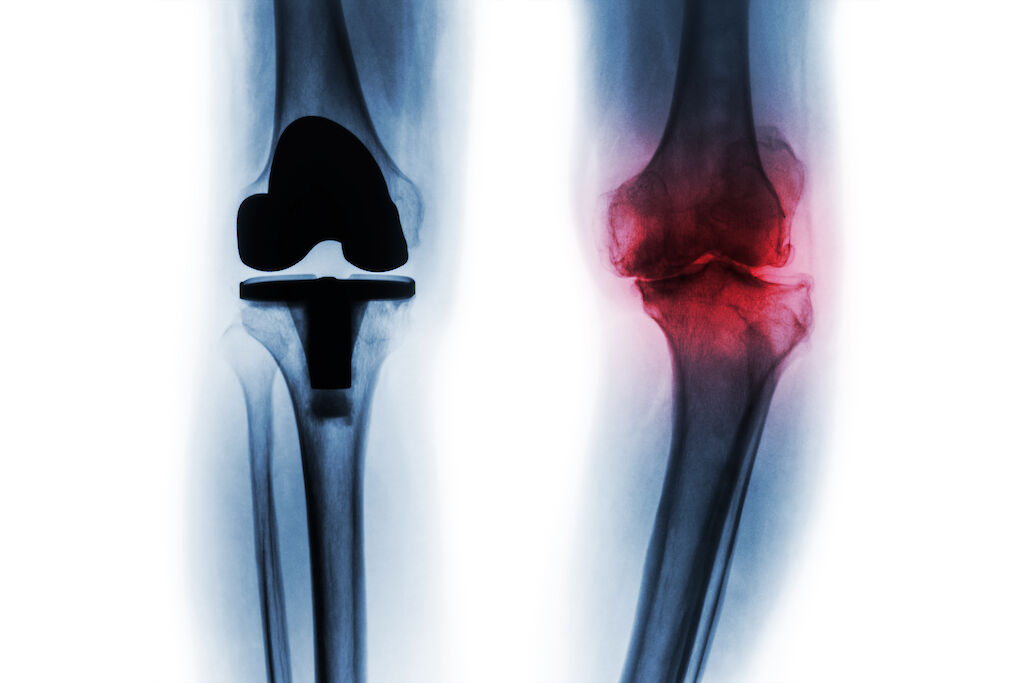

Pääsyä lonkan ja polven tekonivelleikkauksiin halutaan parantaa.

Tekonivelsairaala Orton keskittyy lonkan ja polven tekonivelleikkauksiin. Toiminnan on tarkoitus alkaa 1. huhtikuuta. Samalla Orton oy:n nykymuotoinen toiminta yksityissairaalana päättyy.